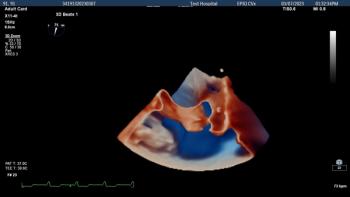

Reportedly providing enhanced imaging of structural heart disease, the minimally invasive X11 4t Mini 3D TEE ultrasound transducer facilitates use of the technology in smaller pediatric patients as well as high-risk ICU patients.